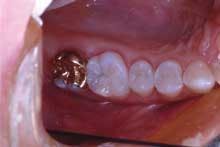

Figure 4 shows the final restorations - a high-strength, all-ceramic crown (Lava, 3M) and a conservative Class II direct composite (Premise, Kerr).

From a business standpoint in our office, the fees for an all-ceramic crown, a build-up, and a three-surface Class II composite total $1,618. If they are done at the same time, we will schedule 2.25 hours of total chairtime. This comes out to $719 per hour. If we were to do these restorations separately, our total chair time would be three hours. Our hourly productivity would then be reduced to $539 per hour. From the patient's standpoint, it would require three visits to our office instead of two, as well as having an additional injection.